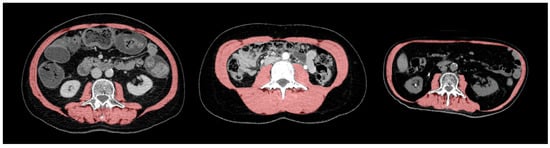

2.2. Sarcopenia Assessment

- Ibtehaz, N.; Rahman, M.S. MultiResUNet: Rethinking the U-Net architecture for multimodal biomedical image segmentation. Neural Netw. Off. J. Int. Neural Netw. Soc. 2020, 121, 74–87. [Google Scholar] [CrossRef] [PubMed]

- Koitka, S.; Kroll, L.; Malamutmann, E.; Oezcelik, A.; Nensa, F. Fully automated body composition analysis in routine CT imaging using 3D semantic segmentation convolutional neural networks. Eur. Radiol. 2021, 31, 1795–1804. [Google Scholar] [CrossRef] [PubMed]

- Graffy, P.M.; Liu, J.; Pickhardt, P.J.; Burns, J.E.; Yao, J.; Summers, R.M. Deep learning-based muscle segmentation and quantification at abdominal CT: Application to a longitudinal adult screening cohort for sarcopenia assessment. Br. J. Radiol. 2019, 92, 20190327. [Google Scholar] [CrossRef]

- Burns, J.E.; Yao, J.; Chalhoub, D.; Chen, J.J.; Summers, R.M. A Machine Learning Algorithm to Estimate Sarcopenia on Abdominal CT. Acad. Radiol. 2020, 27, 311–320. [Google Scholar] [CrossRef]